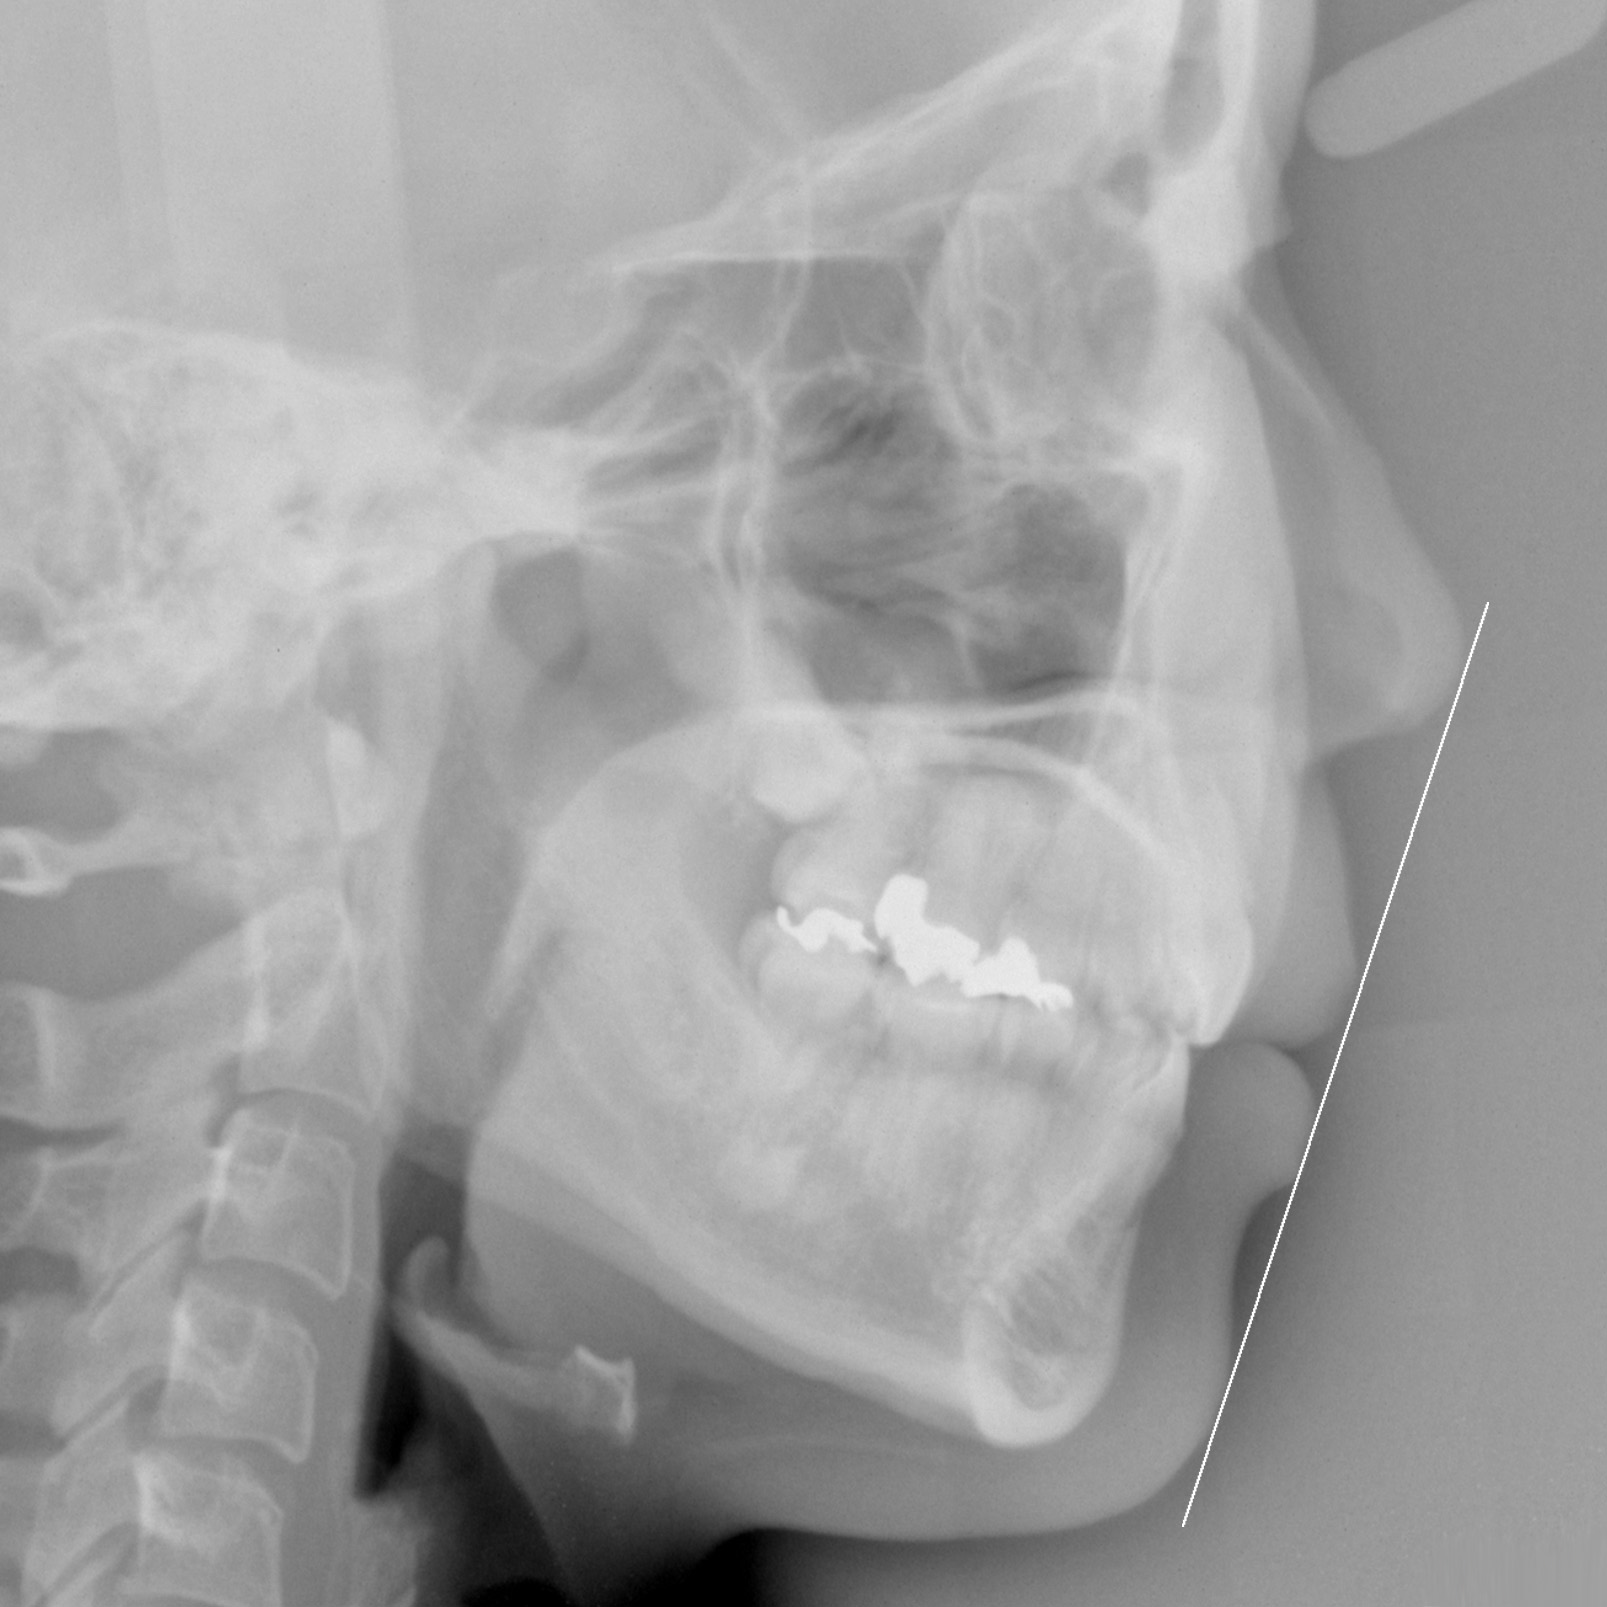

新着情報 939 治療後セファロ側面 – コピー Tweet 投稿日 : 2021年09月28日(火)カテゴリー : コメントを残す コメントをキャンセルメールアドレスが公開されることはありません。 * が付いている欄は必須項目ですコメント 名前 * メール * サイト 30歳 女性「 口もと を下げたい 」( 上下顎前突症 ) ≫